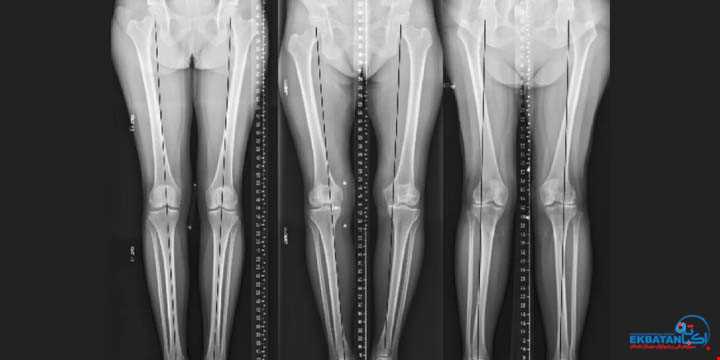

درمان پا پرانتزی و پا ضربدری در کودکان

رادیولوژی اکباتان - مرکز تخصصی بررسی الاینمنت اندام تحتانی با دیتکتور Long iRay و اندازه گیرهای دیجیتال دقیقمقدمهالاینمنت (Alignment) یا راستای اندام ...

نقش رادیوگرافی الاینمنت (Three Joint View) در پا پرانتزی و پا ضربدری کودکان

پا پرانتزی و پا ضربدری؛ از مشکلات رایج دوران رشد کودکان می باشد.پا پرانتزی (Genu Varum) و پا ضربدری (Genu Valgum) از شایع ترین ناهنجاری های محور اندام ...